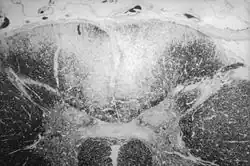

| Section of human skull damaged by late stages of neurosyphilis | |